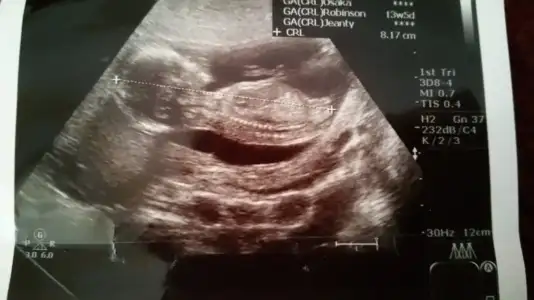

Kızlar ben geldim doktor %90 kız dedi buda foto..

Hayirli olsun canim ben sana neden yorum yaapmadiim ecaba genelde herkese yapiyorum .. gervekte bu resimde nubu paralel kiz oldu nekafar net .. bu fikirde guzel arkadaslar cinsiyeyi ogrenen fotosuda koyarsa hem dahada tecbubeleniriz..

Kizlar 12 haftalik hamileyim. Benim goruntulere de bi baksaniza tahminleriniz neler??